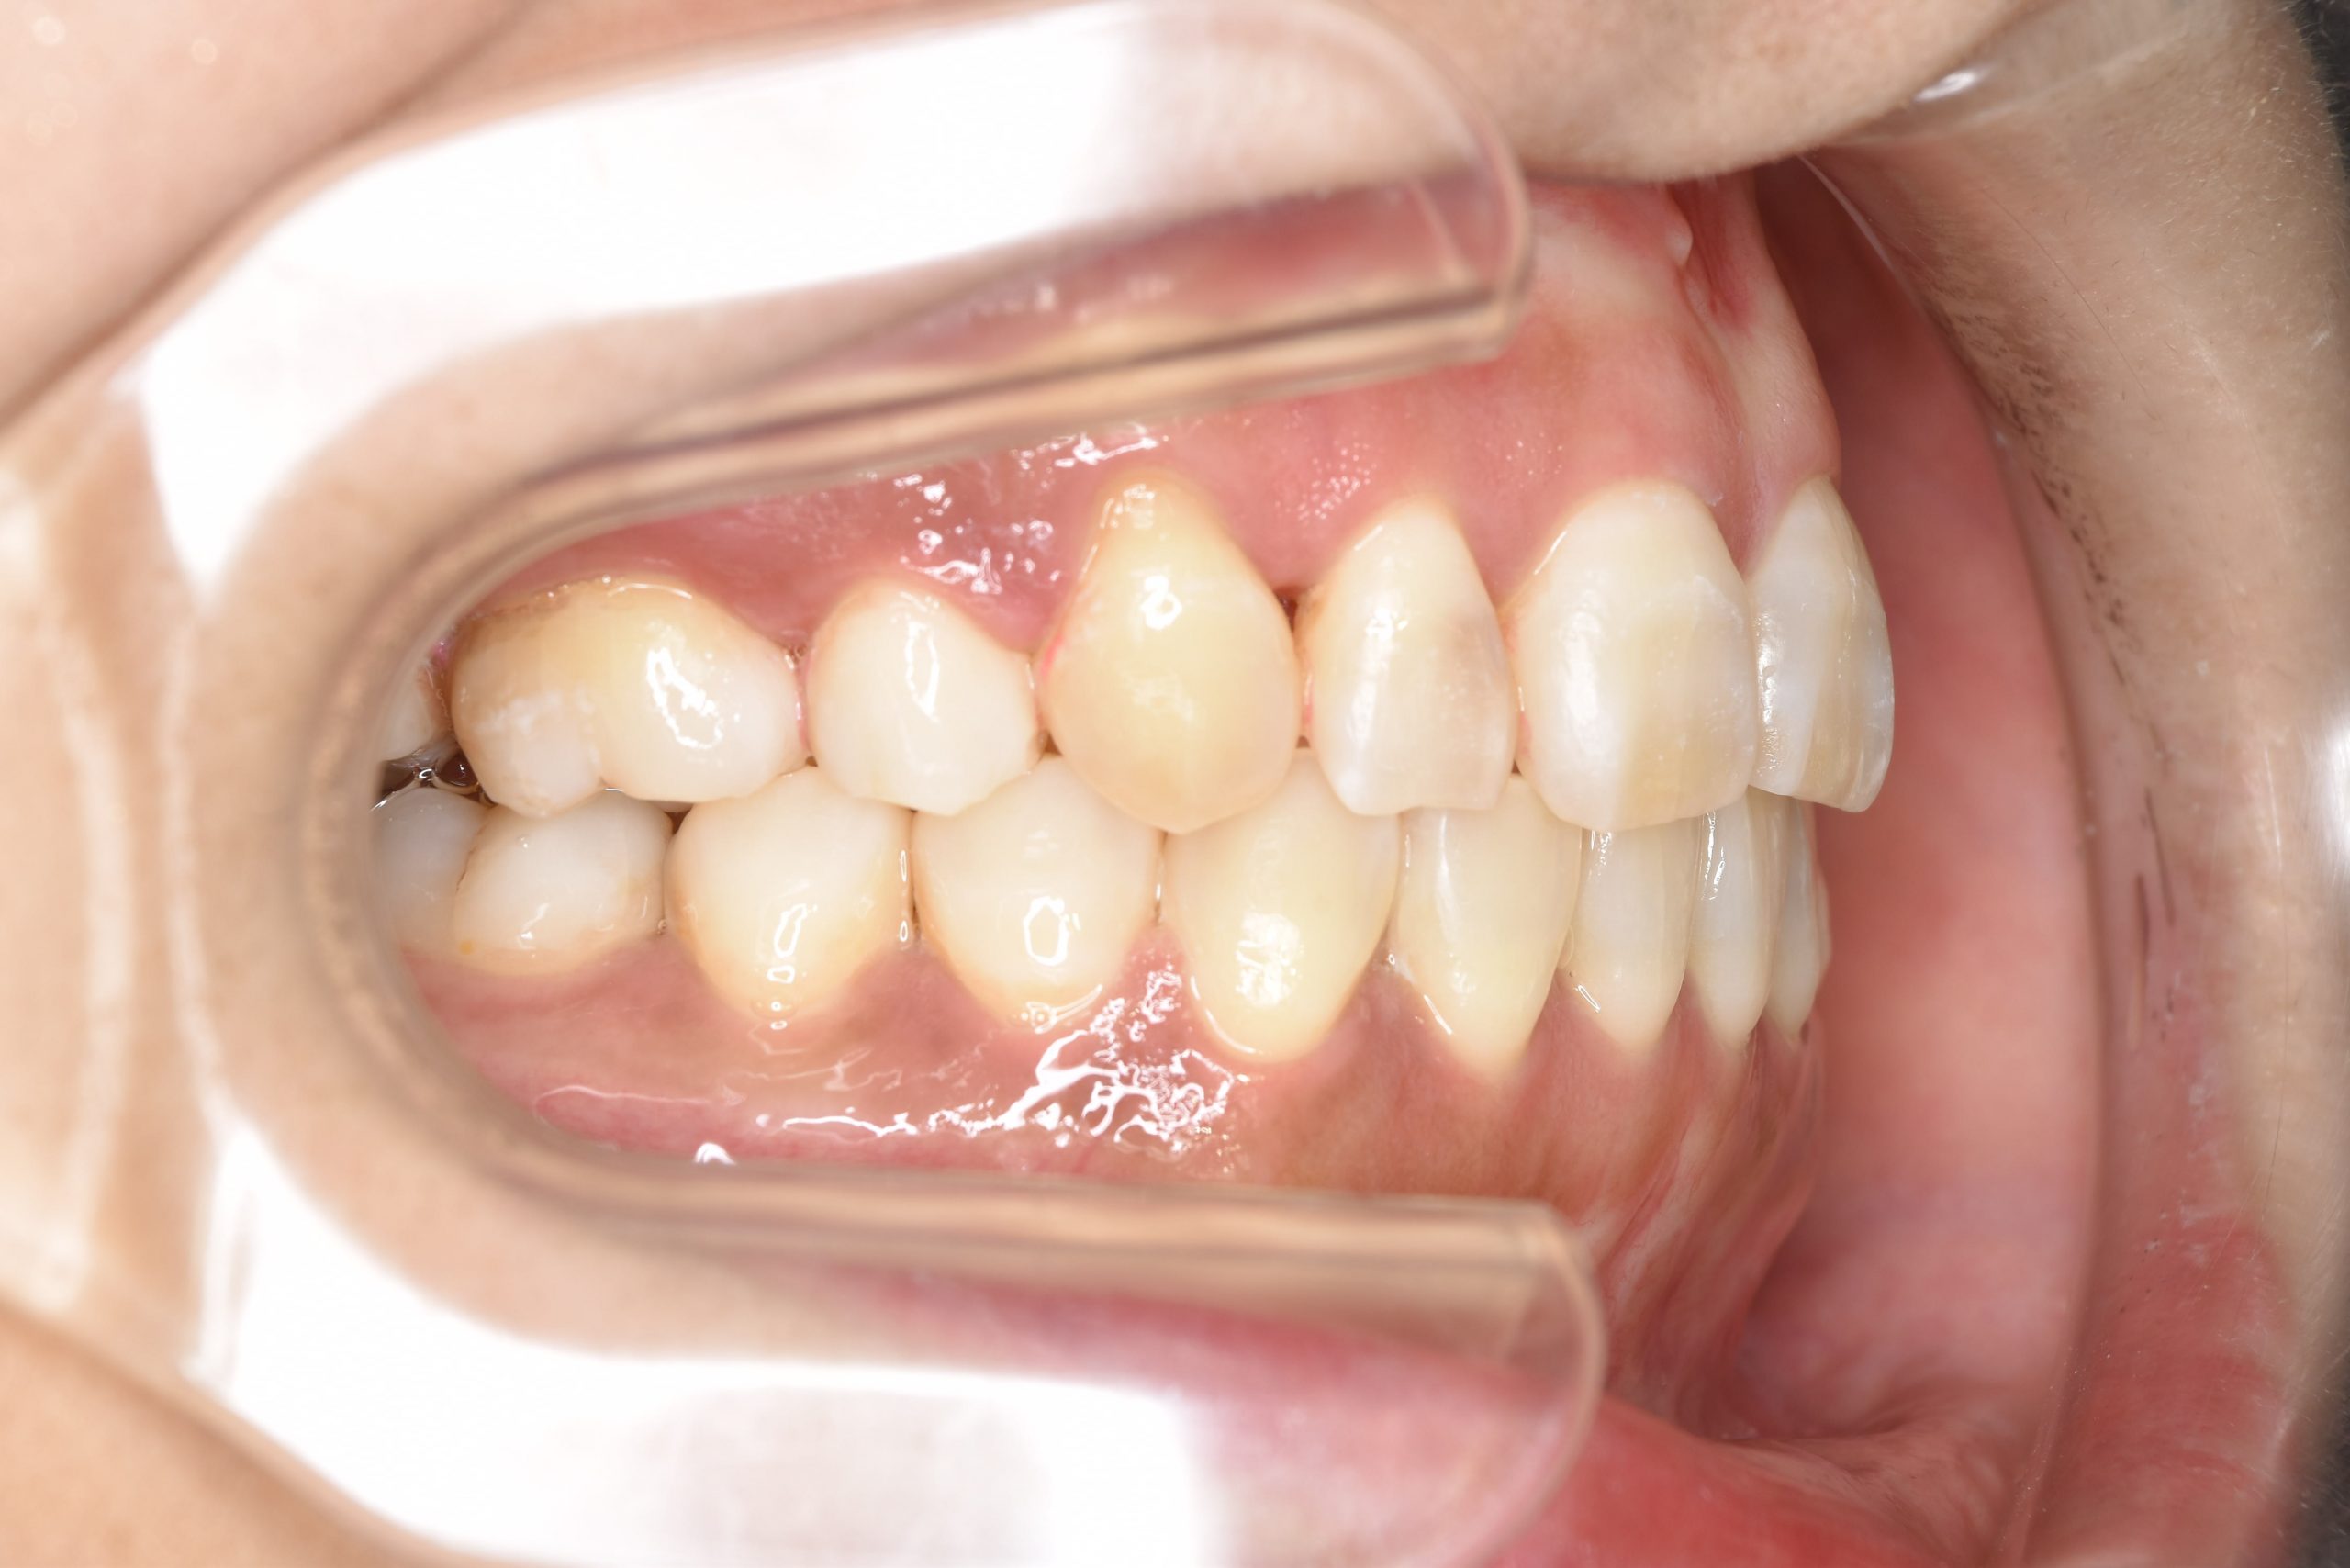

全顎ワイヤー矯正 症例_141

主訴 八重歯|上下センターがずれている

施術内容 成人矯正1期治療

治癒期間 4年10ヶ月間

費用 1,106,560円(税込)